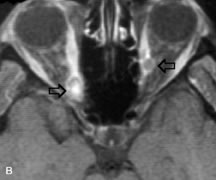

Breast carcinoma metastatic to the orbit has been demonstrated to be hypointense to the surrounding orbital fat on T1-weighted studies and hyperintense on T2-weighted images and has an affinity to the extraocular muscles (Fig. 20).50,64 The MRI characteristics of prostate carcinoma metastatic to the orbit have been described as involving the greater and lesser wing of the sphenoid, orbital roof, and optic canal. Diffuse bone hypertrophy with isointense or slightly hyperintense tissue on T1-weighted images represents the osteoblastic carcinomatous bone infiltration. Contrast enhancement is variable on T1-weighted and fat-suppressed images.65

Fig. 20. A. T1-weighted MR scan demonstrates nodular enlargement of both medial rectus muscles (arrows). B. T1-weighted fat-suppressed contrast-enhanced scan confirms the presence of small metnstatic deposits within the muscles (open arrows).

Most other metastatic tumors also have a lower intensity signal on T1-weighted images and appear to displace or infiltrate normal orbital structures; however, their signal characteristics are variable on T2-weighted MR images.66 Many metastatic tumors demonstrate bright contrast enhancement with Gd-DTPA.